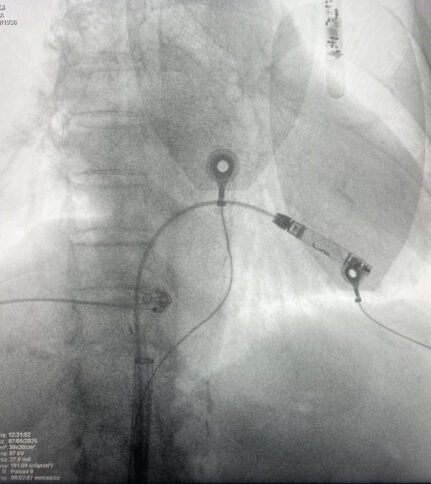

REGGIO CALABRIA Sono stati eseguiti nei giorni scorsi, presso la U.O.C. di Cardiologia-UTIC e Cardiostimolazione di Polistena diretta dal Primario Carmelo Massimiliano Rao, i primi due impianti di pacemaker senza fili, dando l’avvio così a una nuova stagione che vede il presidio di Polistena allinearsi sempre di più ai migliori standard nazionali ed europei. Gli interventi effettuati dall’equipe certificata di Cardiostimolazione composta da Sebastiano Quartuccio, Mario Spanò, il coordinatore infermieristico Girolamo Guerrisi e con l’assistenza tecnica del dottor Andrea Brunori hanno garantito il posizionamento con successo in due pazienti di un nuovo pacemaker miniaturizzato senza fili, circa dieci volte più piccolo di un pacemaker normale, e che grazie alle sue caratteristiche tecnologiche viene posizionato direttamente all’interno del ventricolo destro del cuore con una procedura mini-invasiva, utilizzando la vena femorale, attraverso uno speciale introduttore, mediante una piccola incisione nell’inguine.

L’impianto di pacemaker tradizionale può presentare criticità, sia in fase operatoria che nel follow-up successivo, dato che vi è necessità di un approccio chirurgico con incisione della cute e conseguente sviluppo di cicatrice. Nel follow-up possono verificarsi complicanze a livello locale legate alla presenza del generatore sottocutaneo e degli elettrocateteri. I vantaggi invece dei nuovi pacemaker leadless sono legati essenzialmente alle loro piccole dimensioni, all’assenza di meccanismi di connessione tra generatore ed elettrodi, alla procedura di impianto mini-invasiva transcatetere, e al minore rischio di infezioni. Questa nuova procedura eseguita invece in anestesia locale, non prevede l’uso di elettrocateteri e non lascia cicatrici esterne. Tra i vantaggi, vi è inoltre il positivo impatto psicologico legato all’assenza di cicatrice (non essendovi necessità di incisione chirurgica) e di tasca sottocutanea.